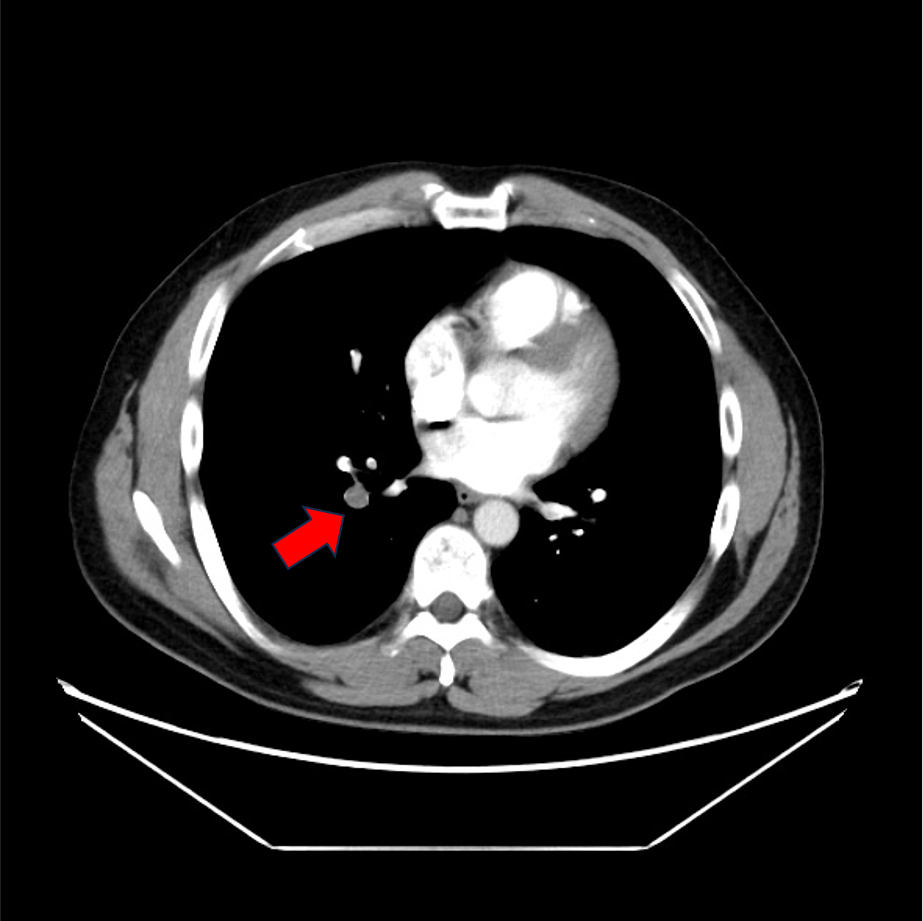

症例は40歳代男性。左下腿の浮腫、疼痛と労作時息切れを認め、血液検査にて血清D-dimerが高値であったため、肺血栓塞栓症の精査目的に造影CTが施行された。両側肺動脈と両側下肢静脈に造影欠損域を認め、それぞれ肺血栓塞栓症、深部静脈血栓症が考えられた。その後、抗凝固療法が施行されて血栓は縮小し、退院となった。

当該疾患の診断における造影CTの役割

肺血栓塞栓症(PE)の診断にはCTが第一選択となる。肺血栓塞栓症の原因の多くは深部静脈血栓症(DVT)であるため、PEが疑われる場合には速やかにDVTの検索も同時に行われることが望ましい。DVTの検査法としては、超音波検査も挙げられるが、胸部の肺動脈相を撮像の後に骨盤部~下肢の静脈相を撮像することで一度に塞栓源の検索が可能となる。これにより速やかな診断と方針決定に寄与することができる。CTではPE、DVTともに血管内の造影欠損を確認することにより診断となる。その他、右心系の負荷評価や他疾患の鑑別も容易になること、低侵襲的に検査できるといった点がCTの利点として挙げられる。一方で、末梢の微小血栓が描出困難な場合や呼吸変動によるアーチファクトで画質低下が生じることがある。また被曝量が比較的多く、臨床情報から適応を判断することが重要である。

CT技術や撮像プロトコル設定について